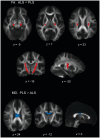

Primary lateral sclerosis is a sporadic disorder characterized by slowly progressive corticospinal dysfunction. Primary lateral sclerosis differs from amyotrophic lateral sclerosis by its lack of lower motor neuron signs and long survival. Few pathological studies have been carried out on patients with primary lateral sclerosis, and the relationship between primary lateral sclerosis and amyotrophic lateral sclerosis remains uncertain. To detect in vivo structural differences between the two disorders, diffusion tensor imaging of white matter tracts was carried out in 19 patients with primary lateral sclerosis, 18 patients with amyotrophic lateral sclerosis and 19 age-matched controls. Fibre tracking was used to reconstruct the intracranial portion of the corticospinal tract and three regions of the corpus callosum: the genu, splenium and callosal fibres connecting the motor cortices. Both patient groups had reduced fractional anisotropy, a measure associated with axonal organization, and increased mean diffusivity of the reconstructed corticospinal and callosal motor fibres compared with controls, without changes in the genu or splenium. Voxelwise comparison of the whole brain white matter using tract-based spatial statistics confirmed the differences between patients and controls in the diffusion properties of the corticospinal tracts and motor fibres of the callosum. This analysis further revealed differences in the regional distribution of white matter alterations between the patient groups. In patients with amyotrophic lateral sclerosis, the greatest reduction in fractional anisotropy occurred in the distal portions of the intracranial corticospinal tract, consistent with a distal axonal degeneration. In patients with primary lateral sclerosis, the greatest loss of fractional anisotropy and mean diffusivity occurred in the subcortical white matter underlying the motor cortex, with reduced volume, suggesting tissue loss. Clinical measures of upper motor neuron dysfunction correlated with reductions in fractional anisotropy in the corticospinal tract in patients with amyotrophic lateral sclerosis and increased mean diffusivity and volume loss of the corticospinal tract in patients with primary lateral sclerosis. Changes in the diffusion properties of the motor fibres of the corpus callosum were strongly correlated with changes in corticospinal fibres in patients, but not in controls. These findings indicate that degeneration is not selective for corticospinal neurons, but affects callosal neurons within the motor cortex in motor neuron disorders.